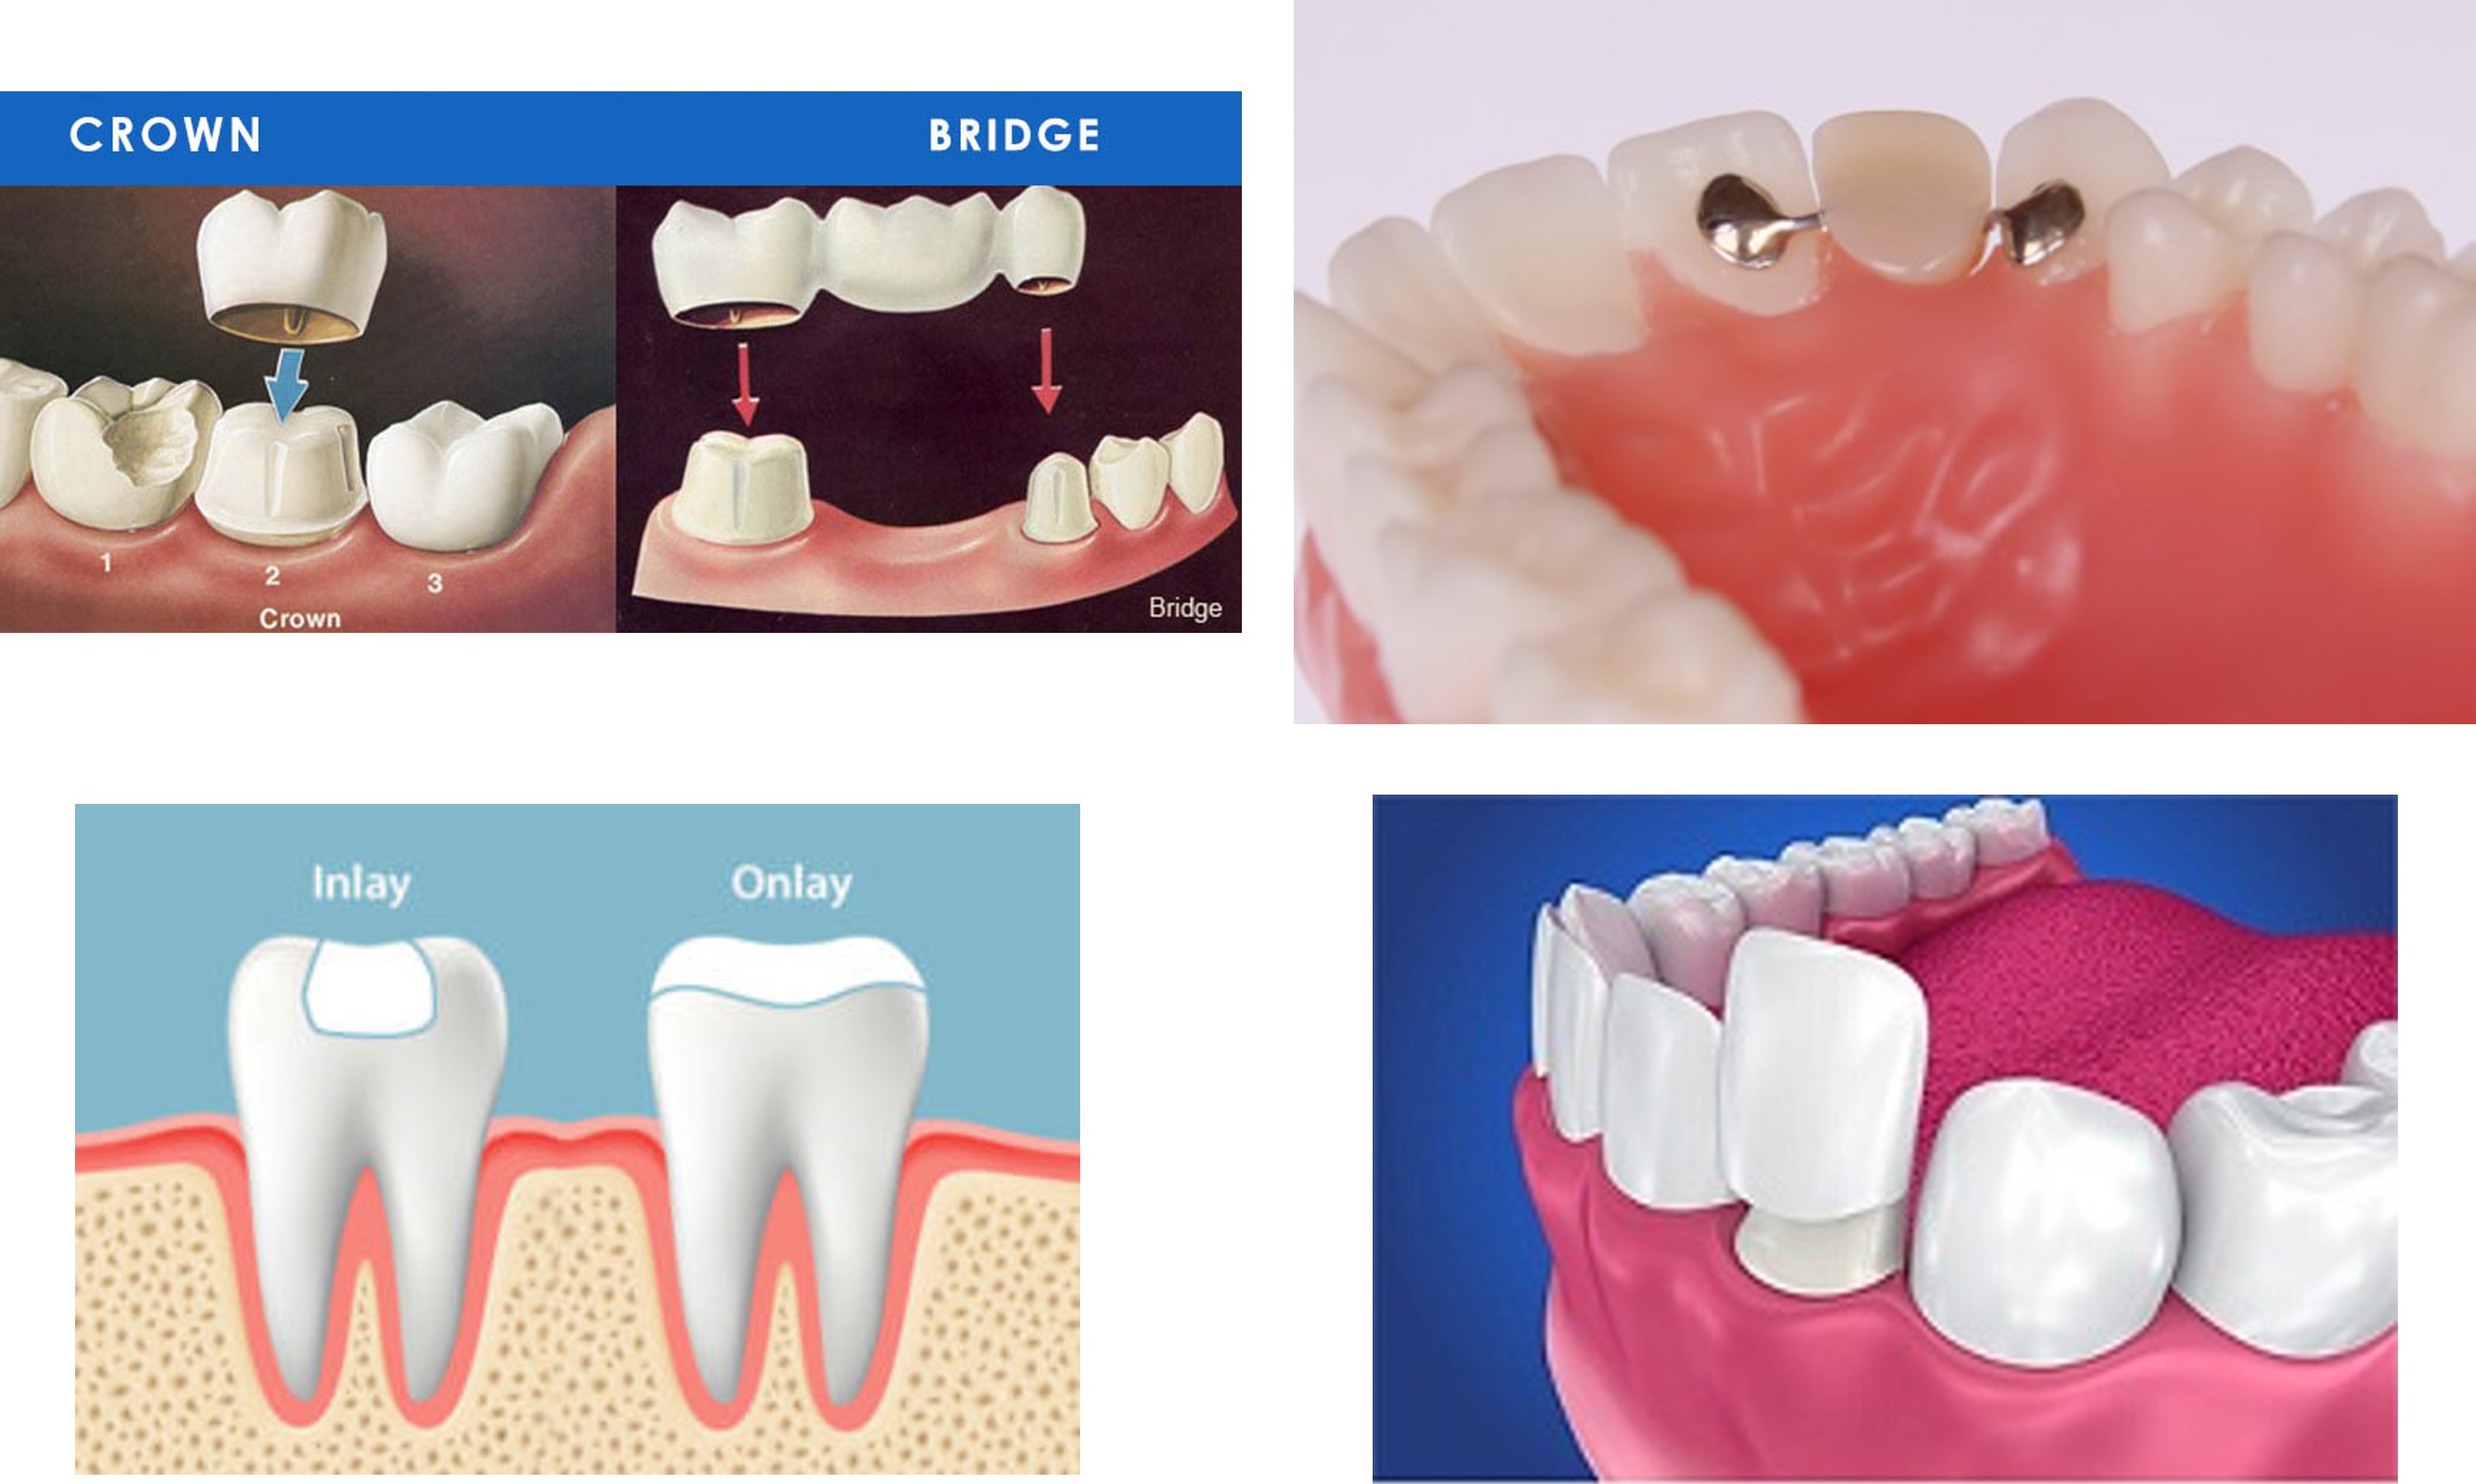

傳統牙冠牙橋

『牙冠』通常針對根管治療後的牙齒或齒質缺損過多的牙齒,以牙冠包覆起來。

『牙橋』則是針對牙齒拔除後之缺牙區,利用前後端之牙齒作支柱牙,才能將義齒固定於其上 ,所以其咀嚼功能很好,而且不必拿下來。

陶瓷崁體、冠塊體

當患者牙齒抽過神經,或蛀洞過大時,傳統上會在真牙外層套上假牙,保護脆弱的牙齒;但假牙對牙齒的修磨過多,已非最理想的治療方式。

陶瓷嵌體,也就是3D齒雕,是利用強度與顏色皆和真牙相仿的陶瓷,如拼圖般補上牙齒的缺損處,不但恢復牙齒強度,也能為患者保留更多的齒質。